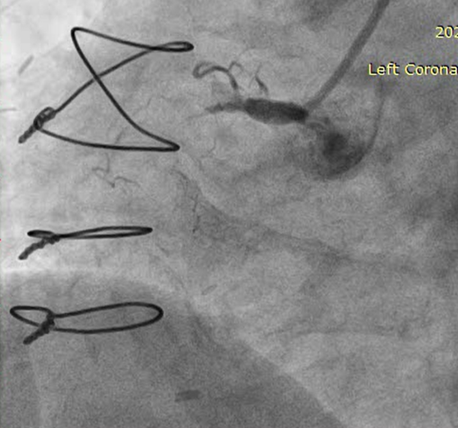

RSVG to Ramus to PLV was engaged with 7F AR-1 guide catheter. Occluded segment in RSVG crossed with Pilot-150 PTCA wire with Caravel micro-catheter and parked into distal RCA. Position of the wire and micro-catheter confirmed with retrograde injection from native LMCA. Retrograde wiring was attempted with Gaia NexT-2, Pilot-150, Pilot-200 PTCA guide wires, but was unsuccessful. Native RCA was engaged with 7F AL 0.75 guide catheter and antegrade wiring was attempted with micro-catheter support and Gaia NexT-2, Pilot-150 followed by Pilot-200 PTCA guide wires, but was unsuccessful. Balloon dilatation was done in proximal RCA with 2.0 x 10 mm SC balloon. Knuckle wire technique was used to cross the lesion from antegrade site but unsuccessful. Finally, lesion crossed with Asahi Gladius MG-14 wire from antegrade approach and wire parked into the RSVG. Micro-catheter exchanged. Serial predilatation was done with 0.75 x 8 mm SC balloon followed by 2.0 x 20 mm SC balloon. IVUS run was taken for vessel size estimation. 3.0 x 48mm DES was deployed from proximal RCA. Post dilatation was done with NC 3.5 x 8 mm balloon. Distal RCA was addressed with 2.75 x 30 mm DEB. Mid RCA was stented with DES 3.00 x 32 mm. Post-dilated with 3.0 x 10 mm NC balloon followed by 3.75 x 8 mm NC balloon. Post-stenting IVUS run showed good stent expansion and apposition. Distal TIMI-III flow was achieved.